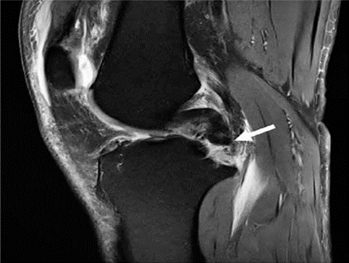

Hình 8. Nước mắt tay cầm xô lệch. A và B là hình ảnh cộng hưởng từ pd xóa mỡ với vết rách tay cầm cho thấy một mảnh sụn dịch chuyển liền kề với dây chằng chéo sau (mũi tên trắng), được gọi là dấu hiệu "dây chằng chéo sau đôi ", cũng như một mảnh sụn bị dịch chuyển trong rãnh liên chất (mũi tên đen). C là hình ảnh pd xóa mỡ với vết rách ở tay cầm cho thấy mảnh bị dịch chuyển ra phía trước (mũi tên trắng), tiếp giáp với sừng trước, được gọi là dấu hiệu "sừng trước kép".

Bác sĩ phẫu thuật có thể thực hiện cắt sụn một phần, cắt bỏ sụn chêm hoặc sửa chữa trực tiếp các vết rách sụn chêm. Tiêu chuẩn đánh giá rách sụn chêm sau phẫu thuật trở nên khó áp dụng vì hình dạng sau phẫu thuật của sụn chêm trùng với tiêu chuẩn chẩn đoán rách sụn chêm. Khi phẫu thuật cắt một phần khum, tín hiệu bất thường ban đầu là nội tạng bên trong sụn chêm có thể được chuyển thành tín hiệu chạm vào bề mặt trên hoặc bề mặt dưới. Mô hạt từ vết rách sụn chêm đang lành cũng có thể có các đặc điểm tín hiệu tương tự như vết rách. Do đó, việc chẩn đoán vết rách sụn chêm còn sót lại hoặc mới trong các trường hợp sau phẫu thuật dựa vào sự hiện diện của các mảnh sụn bị di lệch hoặc các nang thông số, hoặc sự hiện diện của cường độ tín hiệu dịch/gadolinium kéo dài vào sụn chêm (Hình 8)[8].